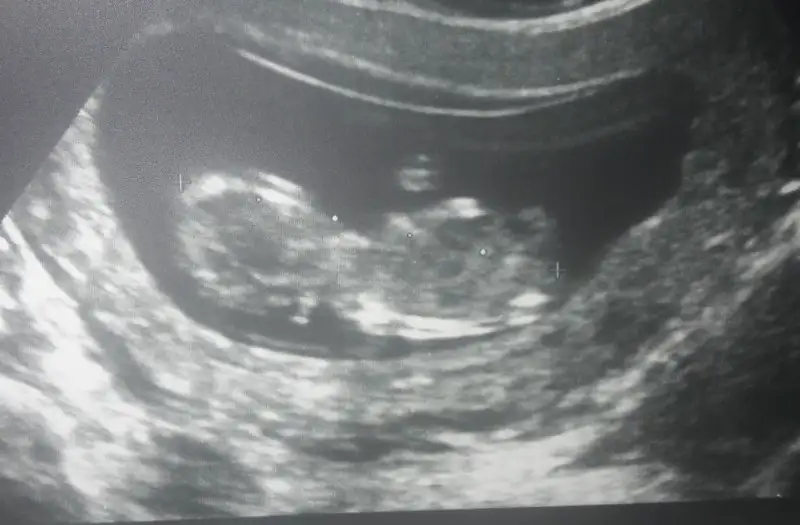

bana mı oyle gelıyor yoksa bu bebısde mı biraz popişini dönmüşEki Görüntüle 2161403 tahminleri bekliyorm![]()

4 boyutlu resmi olsa belli olurduEki Görüntüle 2161403 tahminleri bekliyorm![]()

bana mı oyle gelıyor yoksa bu bebısde mı biraz popişini dönmüş![]()

Artık yavas yavas bellı olmaya baslıyor